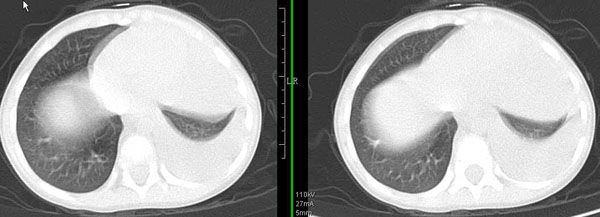

男孩,4岁,发热咳嗽4天。

下面补充ct图片:

左肺门增大,左肺气管阻塞 左肺无肺纹理。右肺代偿性肺气肿。透视图示纵隔摆动。考虑左支气管异物,左肺不张。

此病人是我接手的,发热、咳嗽来做胸透,透视见左侧肺野大部密实,纵隔、心影明显左移,呼吸示纵隔摆动、膈肌矛盾运动(透视下采集了几幅图片),左肺动度明显减弱。询问病人家长,没有吃花生米等呛咳史。由于其影像特征明显,当时诊断:考虑左侧支气管异物并阻塞性肺不张、肺炎。

病人去上级医院支气管镜取出了异物。今天询问上级医院耳鼻喉科主任(是我同学),得知病人异物为胶冻样合并有少许白色粉末,后小儿说晚上喝药片时呛咳过,考虑当时为药片阻塞;另外支气管镜检发现小儿左侧支气管发育略窄,经住院抗炎治疗,现病人基本康复。

多谢各位关注及精彩点评!追踪病人结果时才知道还做过ct检查!对不起!有点晚了,刚刚下载,上传供大家参考!